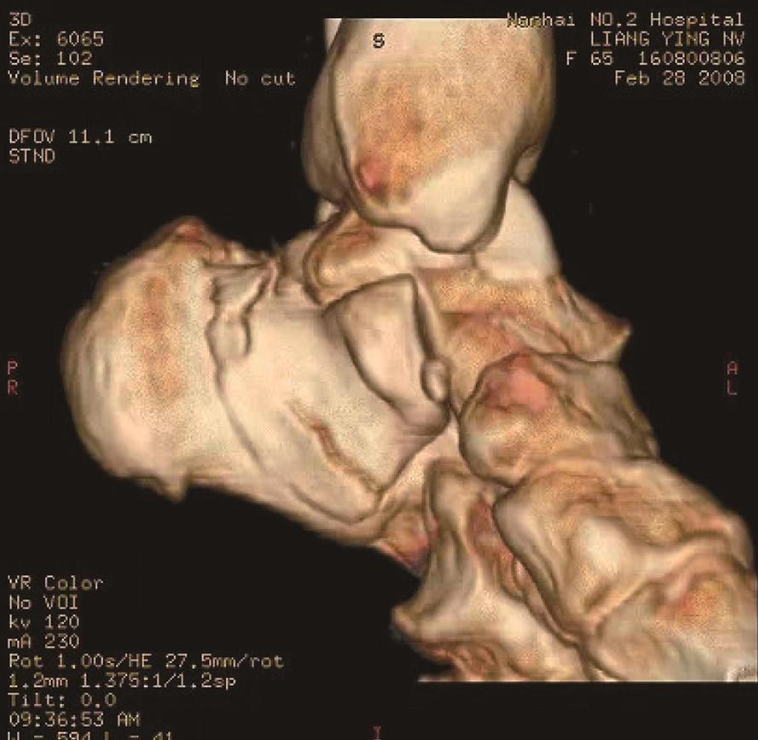

5、CT检查及3D重建:

能够更加直观地观察其三维解剖结构及全面分析跟骨骨折后全骨形态改变。对跟距下关节面出现骨质移位、分离、凹陷性骨折的严重程度及关节内是否有碎骨片存在能做出更准确的判断(图4)。

图4 CT三维重建